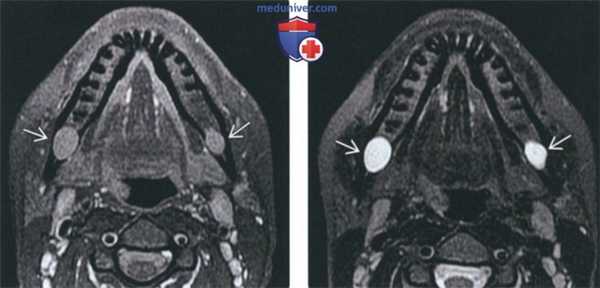

(Слева) МРТ Т1ВИ с КУ, коронарная проекция, этот же пациент. По нижнечелюстному нерву опухоль распространяется в овальное отверстие и тройничную полость. Также опухоль прорастает латеральнее, в твердую мозговую оболочку средней черепной ямки.

(Справа) КТ с КУ в аксиальной проекции, этот же пациент. В области правого отверстия нижней челюсти определяется накапливающая контраст опухоль. В жевательном пространстве видны участки аномального накопления контраста вдоль волокон нижнечелюстного нерва.